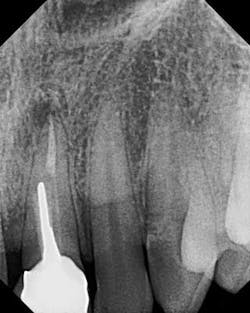

Fig. 4a — Radiograph of failing tooth No. 9